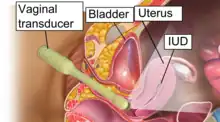

The examination can be performed by transabdominal ultrasonography, generally with a full bladder which acts as an acoustic window to achieve better visualization of pelvis organs, or by transvaginal ultrasonography with a specifically designed vaginal transducer. Transvaginal imaging utilizes a higher frequency imaging, which gives better resolution of the ovaries, uterus and endometrium (the fallopian tubes are generally not seen unless distended), but is limited to depth of image penetration, whereas larger lesions reaching into the abdomen are better seen transabdominally. Having a full bladder for the transabdominal portion of the exam is helpful because sound travels through fluid with less attenuation to better visualize the uterus and ovaries which lies posteriorly to the bladder. The procedure is by definition invasive when performed transvaginally. Scans are performed by health care professionals called sonographers, or gynecologists trained in ultrasound.